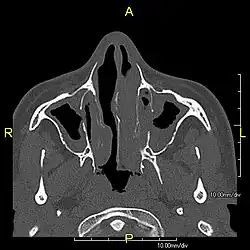

| Complications | Chronic recurrent respiratory infections, including sinusitis, bronchitis, pneumonia, and otitis media.[2] |

When accompanied by the combination of situs inversus (reversal of the internal organs), chronic sinusitis, and bronchiectasis, it is known as Kartagener syndrome[3] (only 50% of primary ciliary dyskinesia cases include situs inversus).[11]